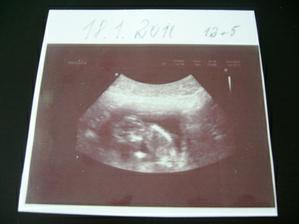

18. 1. 2010, další kontrola u dr., jsme přesně 12+5 jak podle utz, tak podle MS.Vše se zdá v pořádku.Ode dneška jsem v pracovní neschopnosti, takže nám začali trošku delší prázdiny🙂)